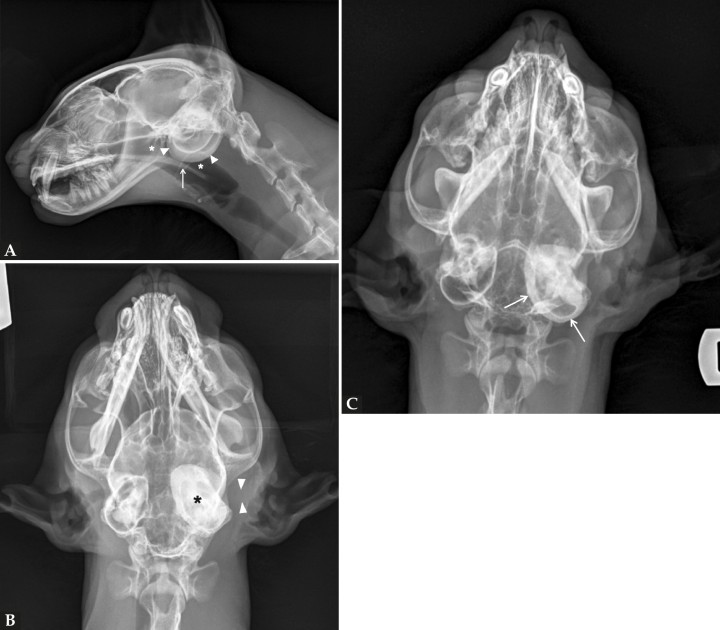

En la proyección lateral (Fig. 2A) se observa con buena definición y sin alteraciones la nasofaringe y paladar blando. Una de las bullas timpánicas (BTs) se aprecia aumentada de opacidad con engrosamiento de su pared ventral, no pudiéndose discernir de qué BT se trata al estar superpuestas. En la proyección dorsoventral (Fig. 2B) se identifica la BT izquierda afectada, encontrándose aumentada su opacidad, con paredes engrosadas y escleróticas. El conducto auditivo externo (CAE) izquierdo se encuentra obliterado y con opacidad tejido blando.

En la proyección rostro 10º ventro-dorsocaudal oblicua con boca cerrada (Fig. 2C) se visualizan con mayor claridad los hallazgos descritos previamente, especialmente el compartimento ventromedial de las BTs y sus paredes.

Figura 2

Mismas radiografías que en la Figura 1. (A) Proyección lateral en la que se aprecia aumento de la opacidad a nivel de las bullas timpánicas con engrosamiento de la pared ventral de una de las bullas (cabezas de flecha), nasofaringe con opacidad aire (asterisco) y paladar blando con grosor y posición normal (flecha). (B) Proyección dorsoventral en la que se identifica que la bulla timpánica afectada es la izquierda, aumentada de opacidad y con engrosamiento y esclerosis de sus paredes (asterisco). Además, el conducto auditivo externo izquierdo se encuentra obliterado, con opacidad tejido blando, sin presencia de gas en su interior (cabezas de flecha). (C) Proyección rostro 10º ventro-dorsocaudal oblicua con boca cerrada en la que se aprecia con mayor claridad el compartimento ventromedial de las bullas y sus paredes (flechas).